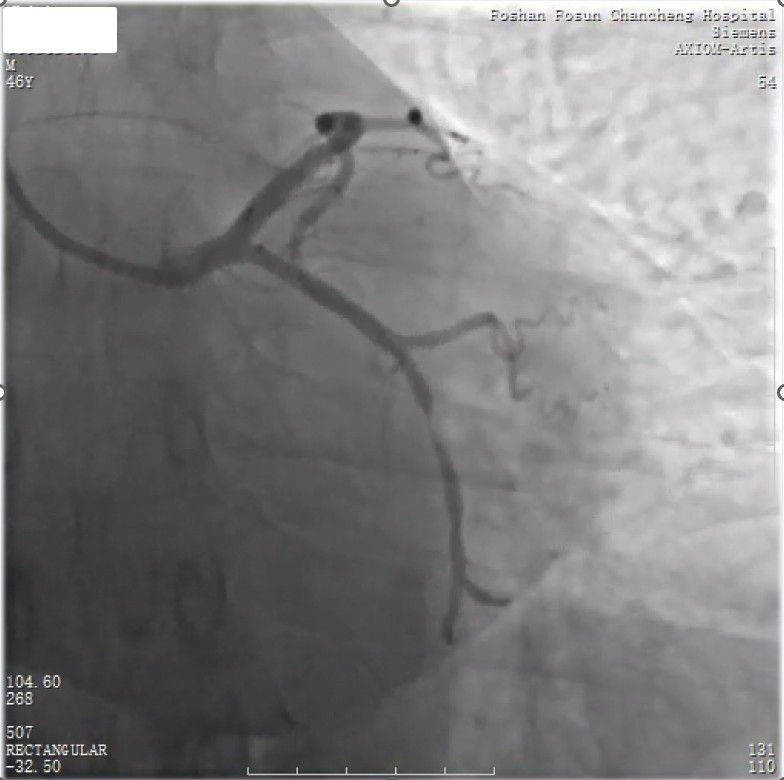

男性,46岁,胸闷1个月,既往高脂血症病史,相关检查:

1、总胆固醇:7.16mmol/L;低密度脂蛋白:4.61mmol/L;甘油三酯:3.46mmol/L;高密度脂蛋白:1.14mmol/L;脂蛋白(a): 364.6mg/L;小而密低密度脂蛋白:697.80mg/L,脂蛋白磷脂酶A2(Lp-PLA2):279 ng/ml (<200);

3、动态心电图:96383次/24小时;平均心率:70次/分;偶发房早,偶发室早;发作性心肌缺血;

4、动态血压:全天平均血压:128/77mmHg;白天血压平均值:129/79mmHg;夜间血压平均值:119/67mmHg;血压负荷:收缩压:白天21.8%;夜间26.7%;舒张压:白天27.4%;夜间26.7%;

5、用药:阿司匹林 100mg QD;替格瑞洛 90mg BID;阿托伐他汀20mg QD;曲美他嗪 35mg BID;雷贝拉唑钠肠溶片 10mg QD;拖来西单抗 150mg/2W

回旋支中远段99%狭窄